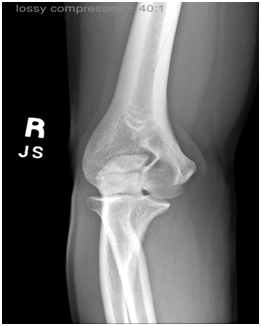

Medial Epicondyle

The patient is an elite HS baseball pitcher who felt a "pop" to the inside of his elbow while throwing a fastball. X-rays showed that he avulsed the medial epicondyle growth center off of the humerus (photo 1). The MRI shows that the bony fragment contains the attachment of the common flexor origin, portions of the growth plate, and the ulnar collateral ligament – aka the tommy john ligament (photos 2,3). Surgery was performed to reduce the avulsed bony fragment with a single screw and repair the ulnar collateral ligament (photos 4,5). Progressive healing occurs over the next 8 weeks and by 12 weeks the player returns to throwing (photos 6,7).